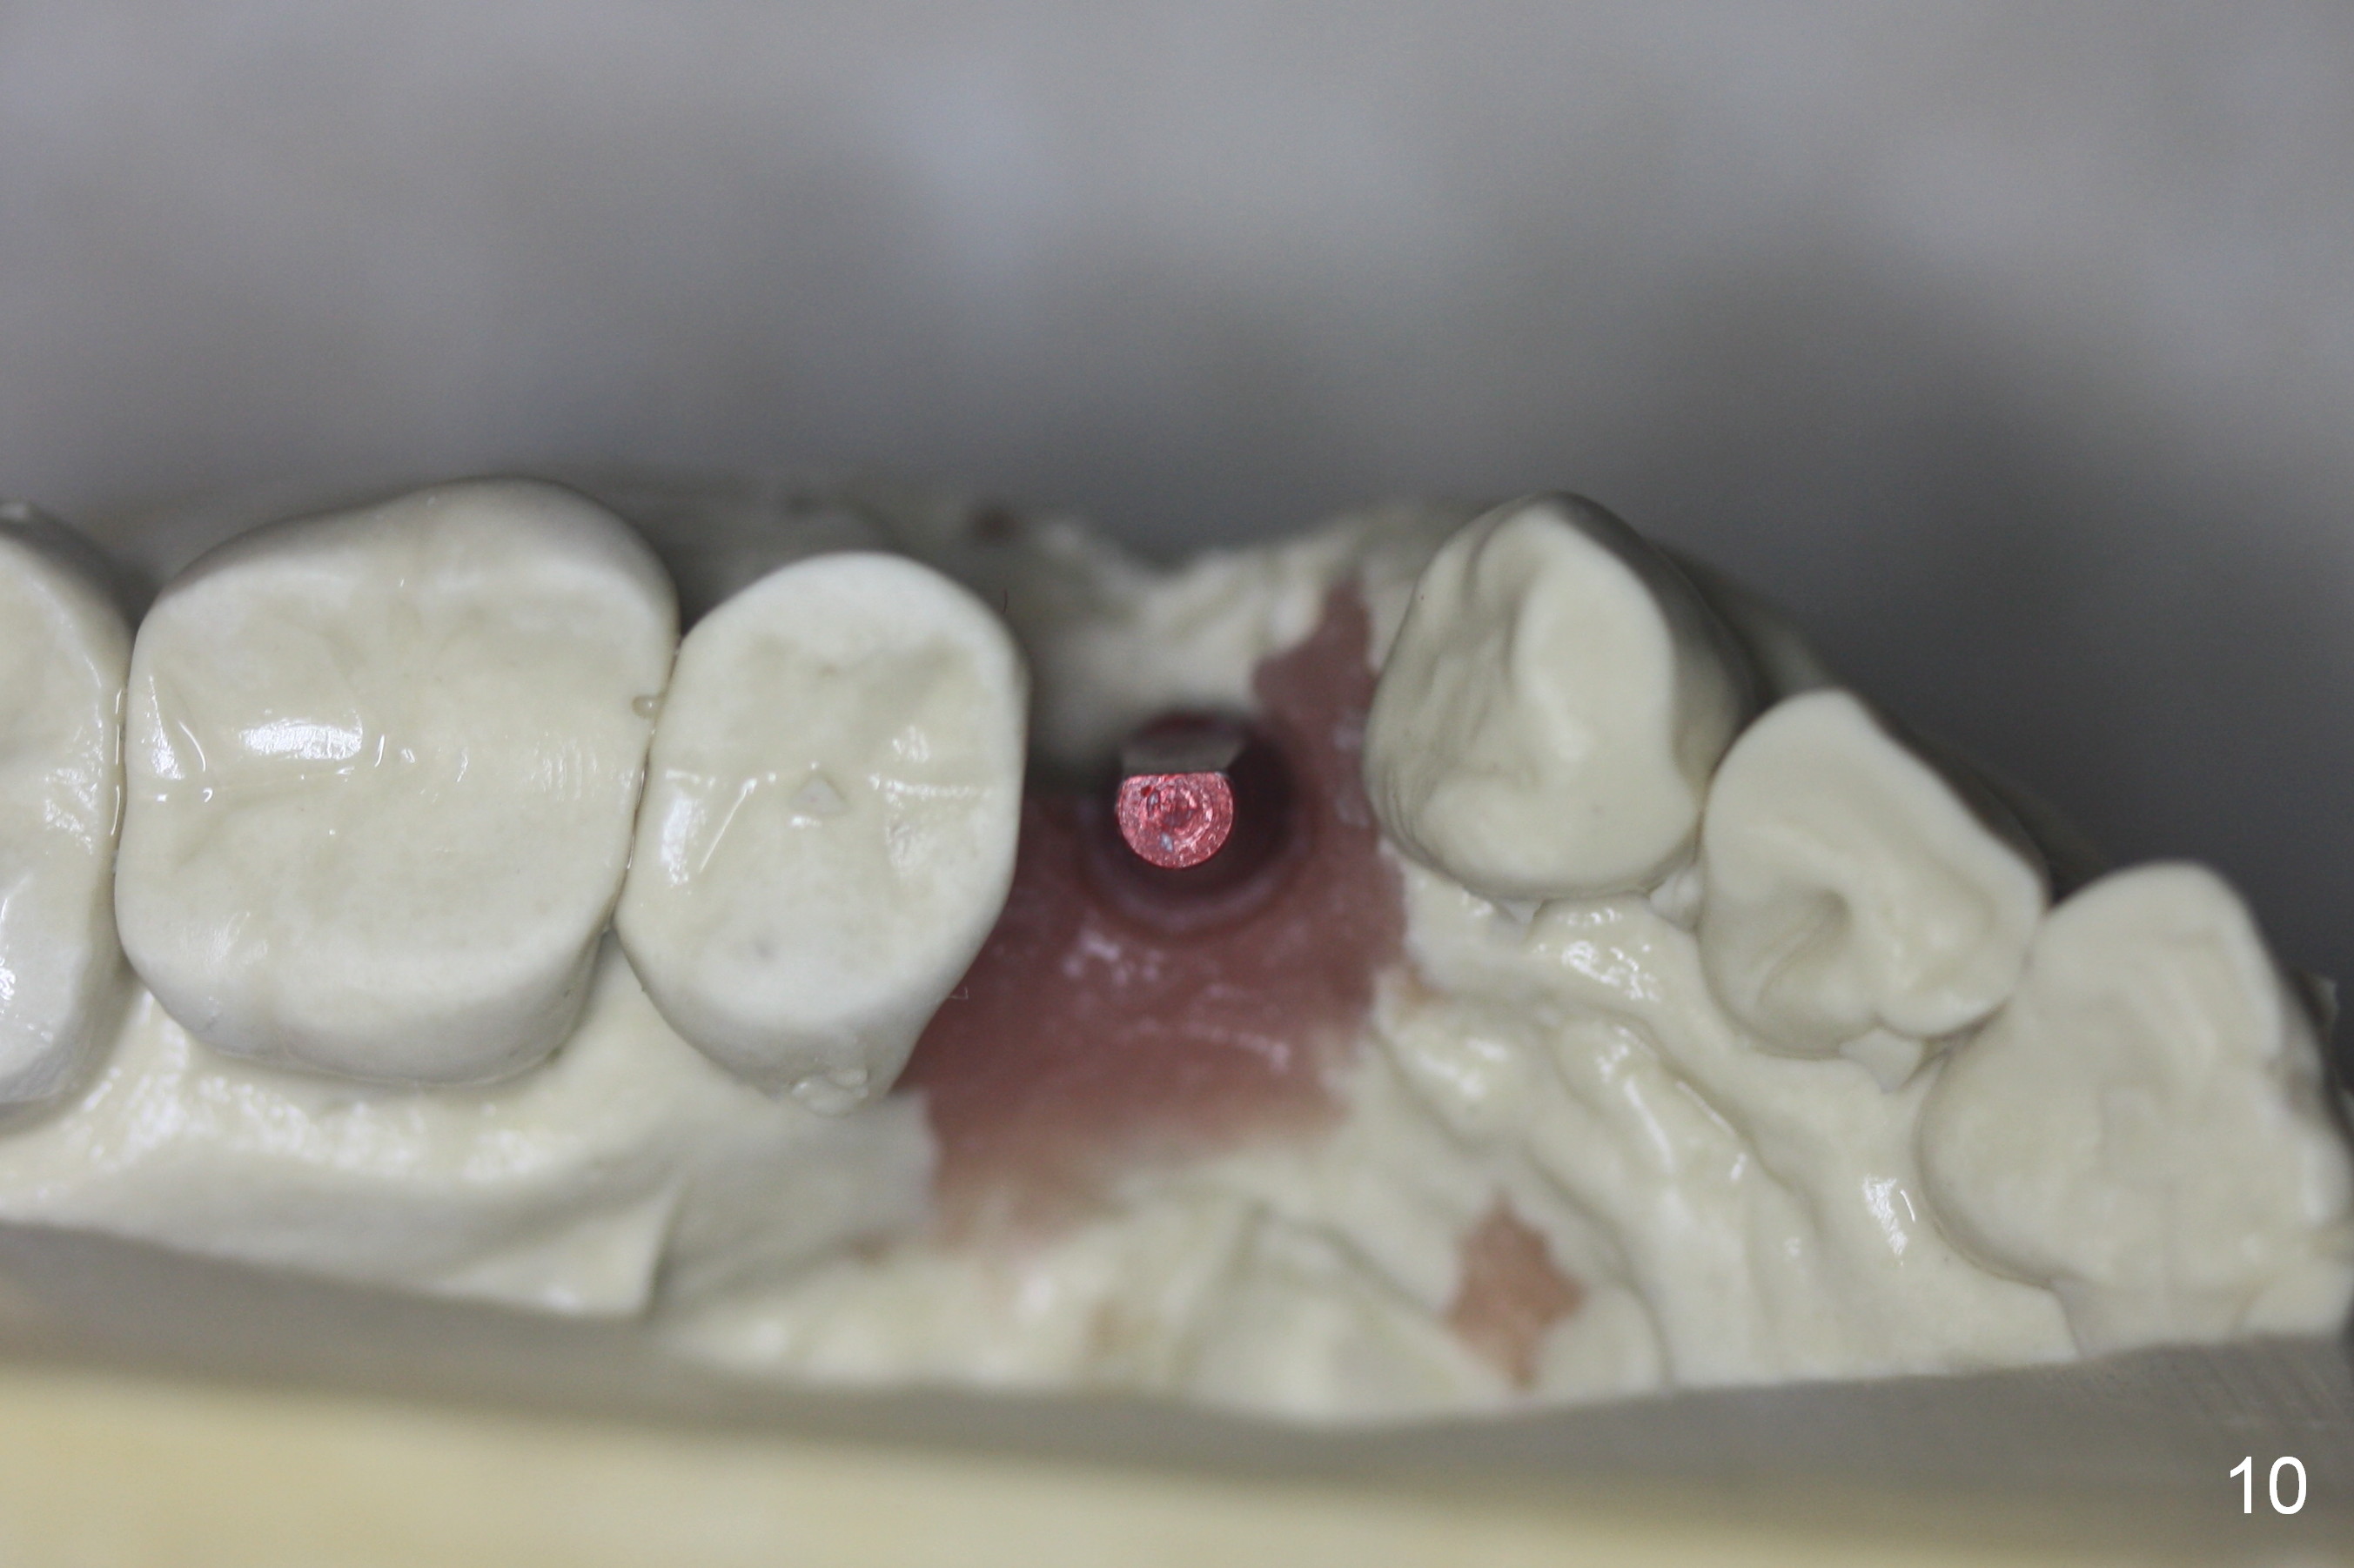

A 68-year-old man has pain and swelling associated with the tooth #5 (Fig.1). The fistula (*) is connected to the periapical radiolucency using a gutta percha (Fig.2 <). There are deep pockets distobuccal and lingual. The lingual root is found to have oblique fracture upon extraction. The distobuccal plate perforates (Fig.3). Collagen plug is placed. The buccal plate is concave (Fig.4) and socket density is low 2.5 months post extraction. Three months post extraction a 4.5x8 mm Bicon implant is placed after reamer and osteotome osteotomy (Fig.6). Bone density around the implant appears to increase 5 months post placement (Fig.7). Porcelain-fused-to-metal crown is cemented 2 weeks later. Bucco-occlusal porcelain chips 2 months post cementation. The patient decides to redo the crown. PA is taken before crown removal (Fig.8: 3 year 10 months post cementation). When a straight abutment is removed (Fig.9 A), a 15° angled abutment has to be used (Fig.10 red) for restoration.